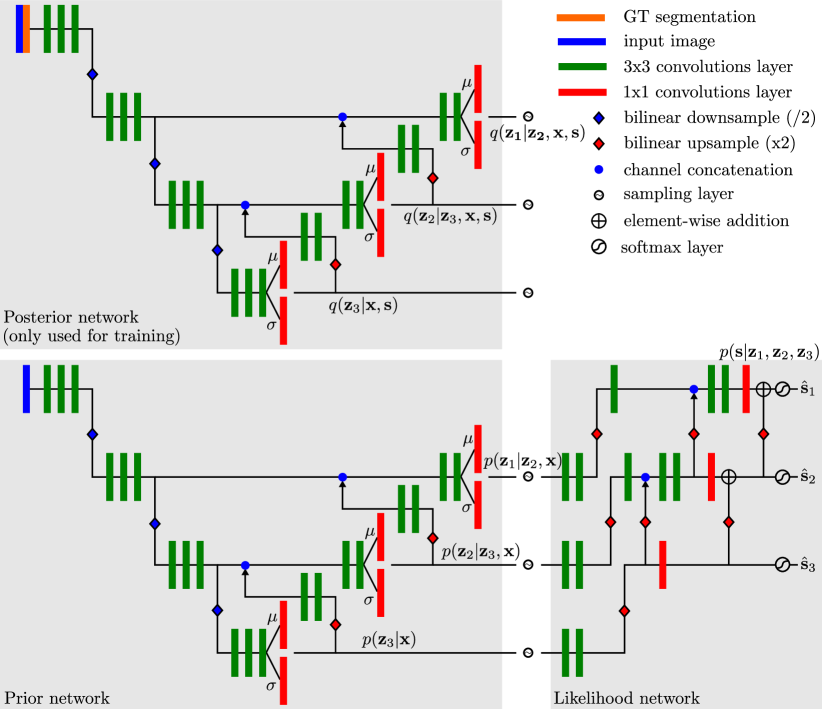

where the are functions parametrised by neural networks. Note that in contrast to the variational autoencoder [3], the are also parametrised by neural networks similar to [4, 8]. Lastly, we model as the usual categorical distribution with parameters (i.e. softmax probabilities) predicted by another neural network. By parametrising all distributions using neural networks, this can be seen as a hierarchical conditional variational autoencoder with the posteriors and priors encoding and into latent representations , and the likelihood acting as the decoder. Our implementation of this model using a neural network for is shown in Fig. 2. In that figure it can be seen that the total number of resolution levels of the network (i.e. number of downsampling steps plus one) can be larger than the number of latent levels. The example in Fig. 2 has a total of 4 resolution levels, of which only are latent levels. We obtained the best results with 7 total resolution levels of which are latent levels. The prior and posterior nets have identical structure but do not share any weights. Similar to previous work, all three subnetworks are used for training but testing is performed by using only the prior and the likelihood networks [3, 8, 4].

From Fig. 2 it can be seen that latent variables will form the skip connections in a U-NET-like architecture. However, unlike [6] and [4], each skip connection corresponds to a latent variable such that no information can flow from the image to the segmentation output without passing a sampling step. We do not map the latent variables to a 1-D vector but rather choose to keep the structured relationship between the variables. We found that this substantially improves segmentation accuracy. As a result, latent variable has a dimensionality of , where is a hyper-parameter and for all experiments, and are the dimensions of the input images. The latent variable is limited to modelling the data at of the original resolution due to the downsampling operations before it. It then passes up the learned representation to the latent space embedding above () to perform a refinement at double the resolution. This continues until the top level is reached. To further enforce this behaviour the likelihood network is designed to generate only residual changes of the segmentation masks for all except the bottom one. This is achieved through the addition layers before the outputs (see Fig. 2). Our model bears some resemblance to the Ladder Network [9] which is also a hierarchical latent variable model where inference results in an autoencoder with skip connections. Our work differs substantially from that work in how inference is performed. Furthermore, to our knowledge, the Ladder Network was never applied to structured prediction problems.

Training and Predictions: We aim to find the neural network parameters which maximise the lower bound in Eq. 2. The analytical form of the individual terms is prescribed by our model assumptions: since the posterior and prior both are modelled by normal distributions, the KL terms can be calculated analytically [3]. Our choice of likelihood results in a cross entropy term , with the predicted segmentation and the corresponding ground-truth. Similar to previous work we found that it is sufficient to evaluate all of the expectations using a single sample [3]. Two deviations from the above theory were necessary for stable training. First, the magnitude of the KL terms depends on the dimensionality of . However, since the dimensionality of in our model grows with , this led to optimisation problems. To counteract this, we heuristically set the weights in Eq. 2. Secondly, to enforce the desired behaviour that should only model the data at its corresponding resolution, we added deep supervision to the output of each resolution level ( in Fig. 2). The cost function used for this is again the cross entropy loss, for , where denotes a nearest neighbour upsampling to match the size of . While can only model the data at a certain resolution, it may ignore this responsibility and focus only on matching the prior and posterior. Deep supervision effectively prevents this behaviour.